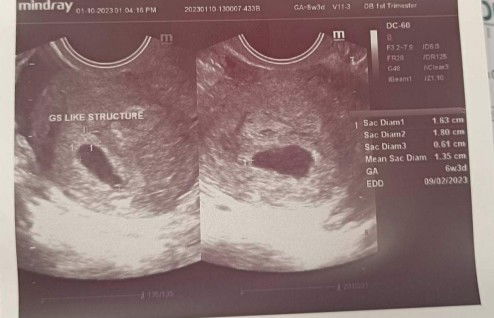

Hello mga mi. FTM to be here. Bothered po ako kasi sa ultrasound 6w3d na pregnancy ko pero GS like structure pa lang daw. Dec 3 po yung LMP ko. 😿

usually nga dapat may sac and heartbeat na eh. ano sabi ng Ob mo? balik ka after 2 weeks if mag develop sya.

parang 5weeks 3days pa lang ng Jan.10,2023